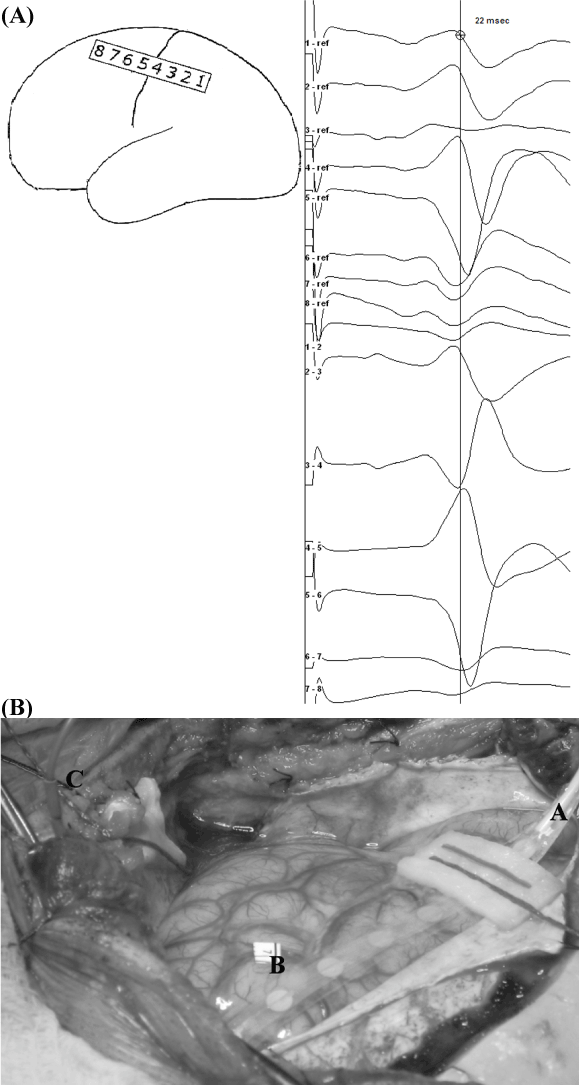

| Figure 1: Recording subdural strip electrode. a- Right median SSEPs phase reversal technique. Referential and bipolar recordings, with the recording strip placed with contact 1 most posterior in the anterior-posterior axis. The referential montage shows a phase reversal at the level of CS: contacts 4 is located postcentrally and contact 5 precentrally. In the bipolar montage, notice the phase reversal at contact 4, pointing towards the most electronegative region, the parietal somatosensory cortex. b- Subdural 8 contact strip electrode placed directly on the cortical surface. Label A shows the extension cable, with contact 8 being the closest. Label B shows a “flag” on the cortical surface, marking eloquent cortex. Label C shows the sterile subdermal needle electrode placed at the margin of the surgical field and connected to the cathode. |